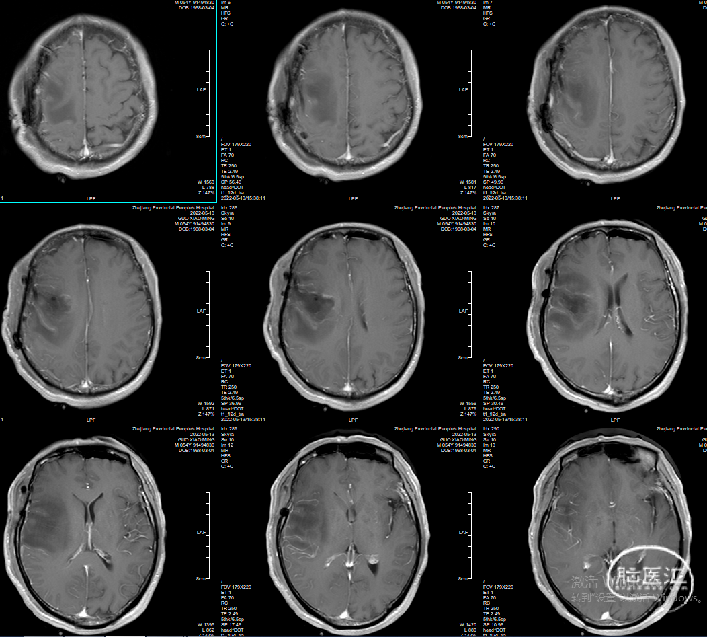

术后MRI: